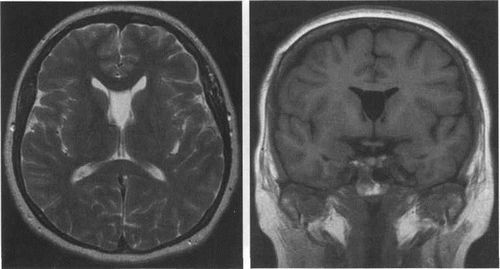

Мал. 3.11. Кіста проміжного вітрила. МРТ /

а - Т2-ВІ, сагітальній площині. Між III шлуночком і задніми відділами стовбура, валика мозолистого тіла розташовується порожнину в формі коми. б - Т2-ВІ, на аксіальному зрізі кіста має трикутну форму, вершина трикутника розташовується на рівні міжшлуночкової отворів.